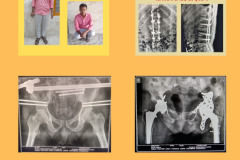

Total Hip Replacement

कूल्हे का प्रत्यारोपण